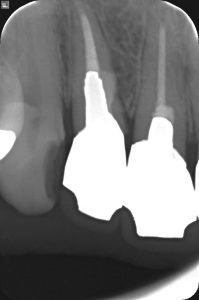

現状 右上2番歯頚部よりにフィステルがある

【透過像が根尖と近心側の2か所に存在】

診断 根尖の病巣はガッタパーチャポイントが明らかにアンダーで空所が認められる。近心側は側枝の可能性、パーフォレーションの可能性がある。フィステルは根尖部ではなく歯頚部に近い部位にあるので近心側の方から由来している可能性がある。